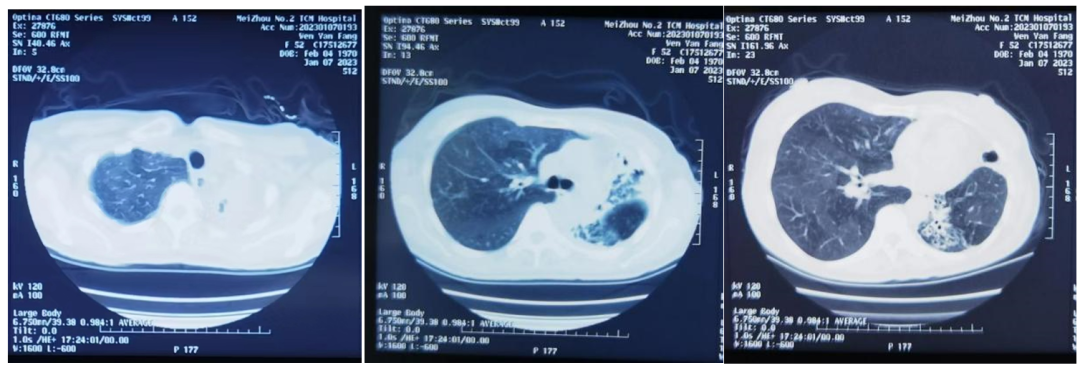

2023-01-07外院胸部CT检查(见图3):1.右肺上中下叶病灶,考虑为炎症(病毒性肺炎),伴支气管扩张;2.左肺上、下叶见条索状、片状密度增高影,考虑为肺结核与肺脓肿需鉴别。

▲图3  2023-01-07胸部CT

本例患者既往胸部CT提示已存在双肺多发支气管扩张并左肺上叶空洞,结合抗酸染色特点,提示该患者为慢性NTM肺病。其肺部影像特征不典型,左肺损毁并支气管扩张病史,反复咳嗽、咳痰伴咳血,极易误诊为肺结核。

肺结核常以低热、盗汗、乏力、消瘦为主要症状,病原学检查检测到结核分枝杆菌,患者有乏力盗汗症状,但无低热消瘦。本例胸部CT显示左肺上、下叶见条索状、片状密度增高影,患者合并新冠感染炎性渗出吸收慢,NTM肺病重叠新冠病毒性肺炎如果不详细结合病史,仅通过影像学手段很难实现对NTM肺病的准确诊断。NTM肺病组织学分为4型:纤维空洞或类结核型、支气管扩张型、结节型和其他类型(包括肺纤维化、肺气肿、肺不张等)。患者既往肺毁损,支气管扩张,可能由黏液阻塞和纤毛功能障碍,气道廓清和局部免疫力下降,存在感染分枝杆菌的危险因素。患者于2012年外院抗结核治疗1年半效果不佳,提示其可能不是肺结核。对于疑难肺部感染,明确可疑病原体,对症治疗对缓解患者病痛尤为关键。